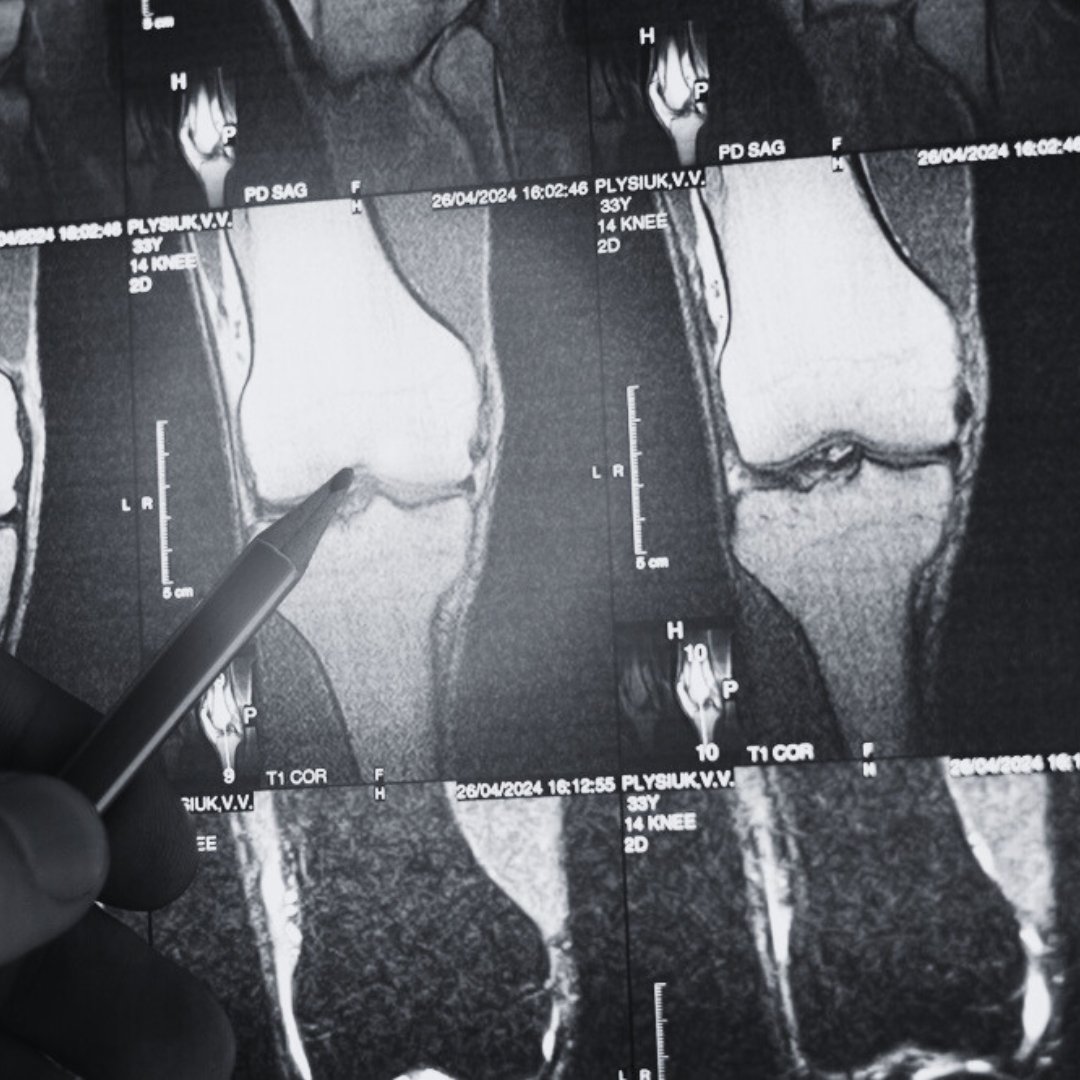

What is Knee Range of Motion (ROM)?

Knee range of motion (ROM) refers to the extent of movement your knee joint can achieve. ROM is measured in degrees, from full extension (straightening your leg) to full flexion (bending your leg). Understanding these measurements can help you set realistic goals for recovery and function.